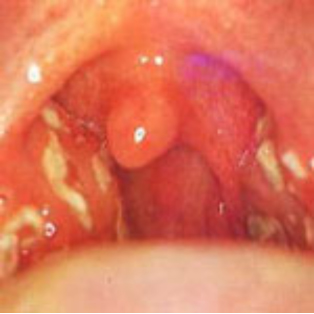

また、『扁桃の外側が腫れて、扁桃が内側に張り出してくる。痛くて食事ができない』といった場合は扁桃周囲膿瘍の可能性があります。

薬剤治療が中心ですが、この場合は切開して排膿出来れば早く治ります。

急性扁桃炎

扁桃周囲膿瘍(右)